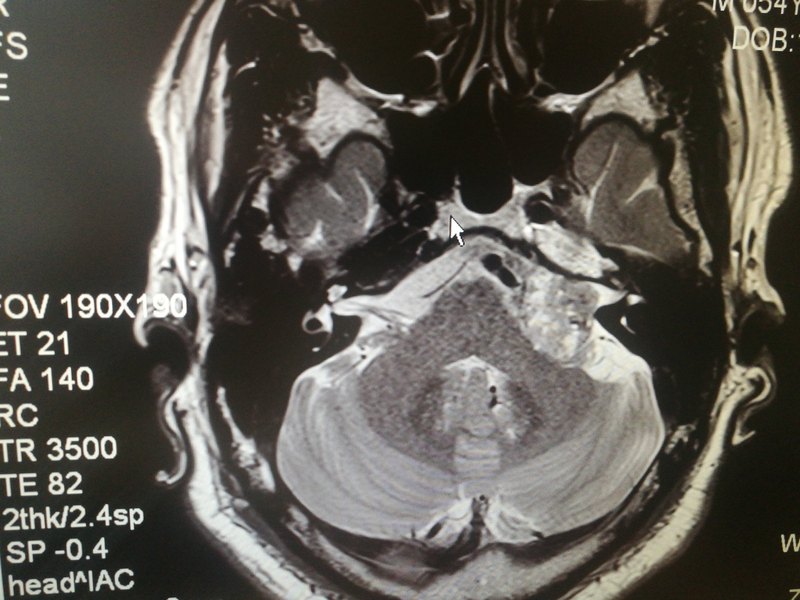

今天又見一患者,左側(cè)耳鳴一年多,在杭州某大醫(yī)院用藥效果不佳,近一周感覺加重來我院就診。無頭痛、眩暈。門診檢查耳道、鼓膜正常,聽力檢查左耳中度感音神經(jīng)性耳聾(平坦型)??紤]病史一年余,周用藥效果不好,有加重趨勢,50多歲,建議內(nèi)聽道磁共振檢查,結(jié)果發(fā)現(xiàn)左側(cè)內(nèi)聽道擴大,橋小腦區(qū)可見直徑3厘米大小占位病變,考慮聽神經(jīng)瘤!建議手術(shù)治療! 對于神經(jīng)性耳鳴三月以上者,醫(yī)生一一^建議常規(guī)內(nèi)聽道磁共振檢查。我們已經(jīng)發(fā)現(xiàn)這類病人誤診誤治十幾例了。都是依靠磁共振檢查發(fā)現(xiàn)的。 臨床上還有病人誤診為突發(fā)性耳聾進行治療而且癥狀也略有改善的。 早年有過病例用CT沒發(fā)現(xiàn)聽神經(jīng)瘤,用磁共振才能發(fā)現(xiàn)的。所以,對于內(nèi)聽道,現(xiàn)在CT基本不用CT,常規(guī)MR。 當(dāng)然,聽神經(jīng)瘤長到比較大的時候,會出現(xiàn)耳鳴、聽力下降,眩暈,甚至頭痛,面癱的時候,診斷就相對容易了! 另外,提醒大家,單側(cè)耳鳴,除了排除聽神經(jīng)瘤,也要警惕鼻咽癌引起的,需要作鼻內(nèi)鏡檢查鼻咽部!